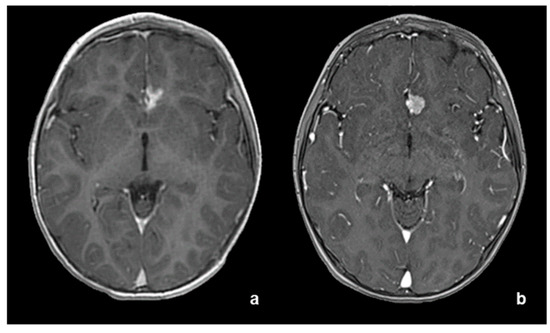

2. Case Report